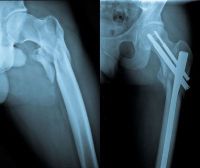

Εξατομικευμένη αρθροπλαστική του ισχίου

Η αρθροπλαστική του ισχίου, η αντικατάσταση δηλαδή της άρθρωσης του ισχίου με την τοποθέτηση τεχνητών εμφυτευμάτων (κράματα μετάλλου και ειδικών συνθετικών υλικών) επιλέγεται σε περιπτώσεις καταγμάτων του αυχένα του μηριαίου, καθώς και σε περιπτώσεις προχωρημένης αρθρίτιδας η οποία δεν ανακουφίζεται σε συντηρητικά μέσα (φυσιοθεραπεία, αντιφλεγμονώδη φάρμακα, άσκηση, δίαιτα).

Η εξατομικευμένη αρθροπλαστική του ισχίου είναι μια σύγχρονη προσέγγιση στη χειρουργική αντικατάσταση του ισχίου, σχεδιασμένη για να παρέχει την υψηλότερη δυνατή ποιότητα και ακρίβεια στην επέμβαση.

O γιατρός λαμβάνει υπόψη τις ιδιαιτερότητες, τις απαιτήσεις και τα μοναδικά ανατομικά χαρακτηριστικά του κάθε ασθενή και εν συνεχεία προβαίνει στην επιλογή των κατάλληλων υλικών και χειρουργικών τεχνικών για την πραγματοποίηση της επέμβασης.

Με την εξατομικευμένη προσέγγιση, και τα σύγχρονα πρωτόκολλα αντιμετώπισης του μετεγχειρητικού πόνου, επιτρέπεται η άμεση κινητοποίηση και φόρτιση του κάτω άκρου, η περίοδος παραμονής στην κλινική είναι μικρότερη, και η ανάρρωση ταχύτερη.